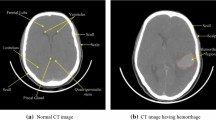

This paper presents an adaptive denoising approach aiming to improve the visibility and detectability of hemorrhage from brain computed tomography (CT) images. The suggested approach fuses the images denoised by total variation (TV) method, denoised by curvelet-based method, and edge information extracted from the noise residue of TV method. The edge information is extracted from the noise residue of TV method by processing it through curvelet transform. The visual interpretation shows that the proposed approach not only reduces the staircase effect caused by total variation method but also reduces visual distortion induced by curvelet transform in the homogeneous areas of the CT images. The denoising abilities of the proposed method are further evaluated by segmenting the hemorrhagic brain area using region-growing method. The sensitivity, specificity, Jaccard index, and Dice coefficients were calculated for different noise levels. The comparative results show that the significant improvement has yielded in the brain hemorrhage detection from CT images after denoising it with the proposed approach.